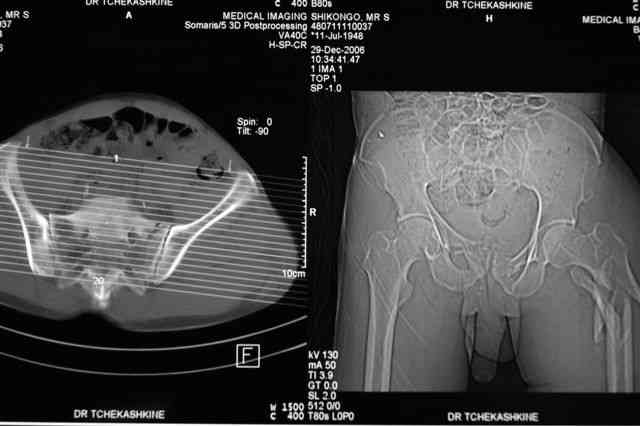

Я помню технику транссакральной фиксации тазового кольца длинными 5 мм Шанцами - повреждения типа В, в этом же случае задний отдел тоже вовлечен

т.е комбинированная нестабильность, поэтому вопрос - достаточно ли только двух Шанцев для стабилизации таза? Что вы думаете об anterior Right SI joint plating + tension band plating from the back.?

Элегантная фиксация, поздравляю.Но ваш случай : одноплоскостная горизонтальная нестабильность Tyle B2.2 отличен от представленного мной - у

моего больного + вертикальная нестабильность за счет повреждения правого крестцово-подвздошного сочленения и перелома заднего отдела подвздошной

кости- С2 тип. Поэтому и возникла дилемма : выбор оптимальной фиксации заднего отдела:

По-поводу фиксации таза спонгиозными винтами. Данный способ все-таки показан для фиксации повреждения крестцово-подвздошного сочленения или переломов крестца. Мне кажется, что в данной случае ситуация иная - имеется перелом "основания" крыла подвздошной кости (в который вовлечена и поверхность, составляющая крестцово-подвздошное сочленение). Не уверен, что фиксация данного повреждения (и заднего полукольца) винтами будет стабильной, так как именно на уровне 1-2 крестцовых позвонков (где обычно вводят винты) линия перелома уходит в латеральном направлении от крестцово-подвздошного сочленения.

PI>По-поводу фиксации таза спонгиозными винтами. Данный способ все-таки показан

для фиксации повреждения крестцово-подвздошного сочленения или переломов крестца. Мне кажется, что в данной случае ситуация иная - имеется перелом

"основания" крыла подвздошной кости (в который вовлечена и поверхность, составляющая крестцово-подвздошное сочленение). Не уверен, что фиксация данного повреждения (и заднего полукольца) винтами будет стабильной, так как

именно на уровне 1-2 крестцовых позвонков (где обычно вводят винты) линия перелома уходит в

латеральном направлении от крестцово-подвздошного сочленения.

Я просмотрел томограммы и у меня создалось впечатление, что винтам есть за что *зацепиться*. В сочетании с 5 мм Шанц винтами, проведенными через нижне-переднюю ость спереди назад через КП сочленения -стабильность тазового кольца должна восстановиться. - Это , конечно, при условии , что закрытая рнепозиция будет успешной.